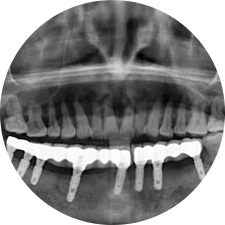

口腔種植是將人工牙根通過(guò)手術(shù)植入牙骨內(nèi),獲得牙槽骨牢固的支持,通過(guò)特殊的裝置和方式連接牙修復(fù)體,獲得與天然牙功能、結(jié)構(gòu)以及美觀相似的效果。

河北惟德口腔醫(yī)院擁有國(guó)內(nèi)豐富的半口/全口、即刻負(fù)重種植案例,十八年案例跟蹤分析,總結(jié)梳理出的各種不同類型的種植案例,Nobel種植體系針對(duì)半口/全口缺牙患者,通過(guò)4-8顆種植體可快速達(dá)到牙齒重建,不僅植入種植體較少,節(jié)省費(fèi)用,手術(shù)時(shí)間更短。

Noble口腔種植體系基本不受年齡限制,適用于缺牙修復(fù),也適用于牙槽骨萎縮、骨質(zhì)疏松、高血壓、糖尿病、超高齡的患者,即種即用,只需少量微小種植體,便可輕松微痛快速重建全口咬合,特殊力學(xué)設(shè)計(jì),針對(duì)許多年紀(jì)較大,骨質(zhì)條件差,身體耐受力差的缺牙老人也能完成“即種即用”,受到廣泛好評(píng)。

惟德口腔種植體系是以患者感受為中心,取代傳統(tǒng)種植牙手術(shù)需要翻瓣、打孔、縫合,術(shù)前、術(shù)中、術(shù)后的繁復(fù)流程,采用3D導(dǎo)航微創(chuàng)準(zhǔn)確種植技術(shù),通過(guò)數(shù)字化CAD/CAM掃描技術(shù)獲得缺牙患者口腔數(shù)據(jù),以數(shù)據(jù)為基礎(chǔ)重建口腔模型進(jìn)行模擬種植。